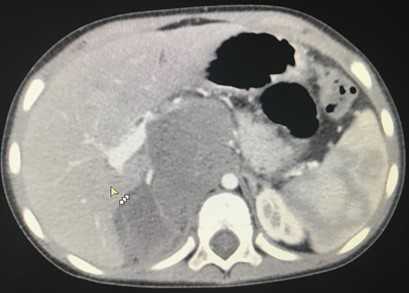

Компьютерная томография брюшной полости и забрюшинного пространства

Компьютерная томография более детально дает информацию об анатомическом отношении опухоли к окружающим тканям и органам, позволяет оценить структуру опухоли (рис. 5).

![Рис. 5. КТ нейрогенного образования забрюшинного пространства справа]()

Рис. 5. КТ нейрогенного образования забрюшинного пространства справа